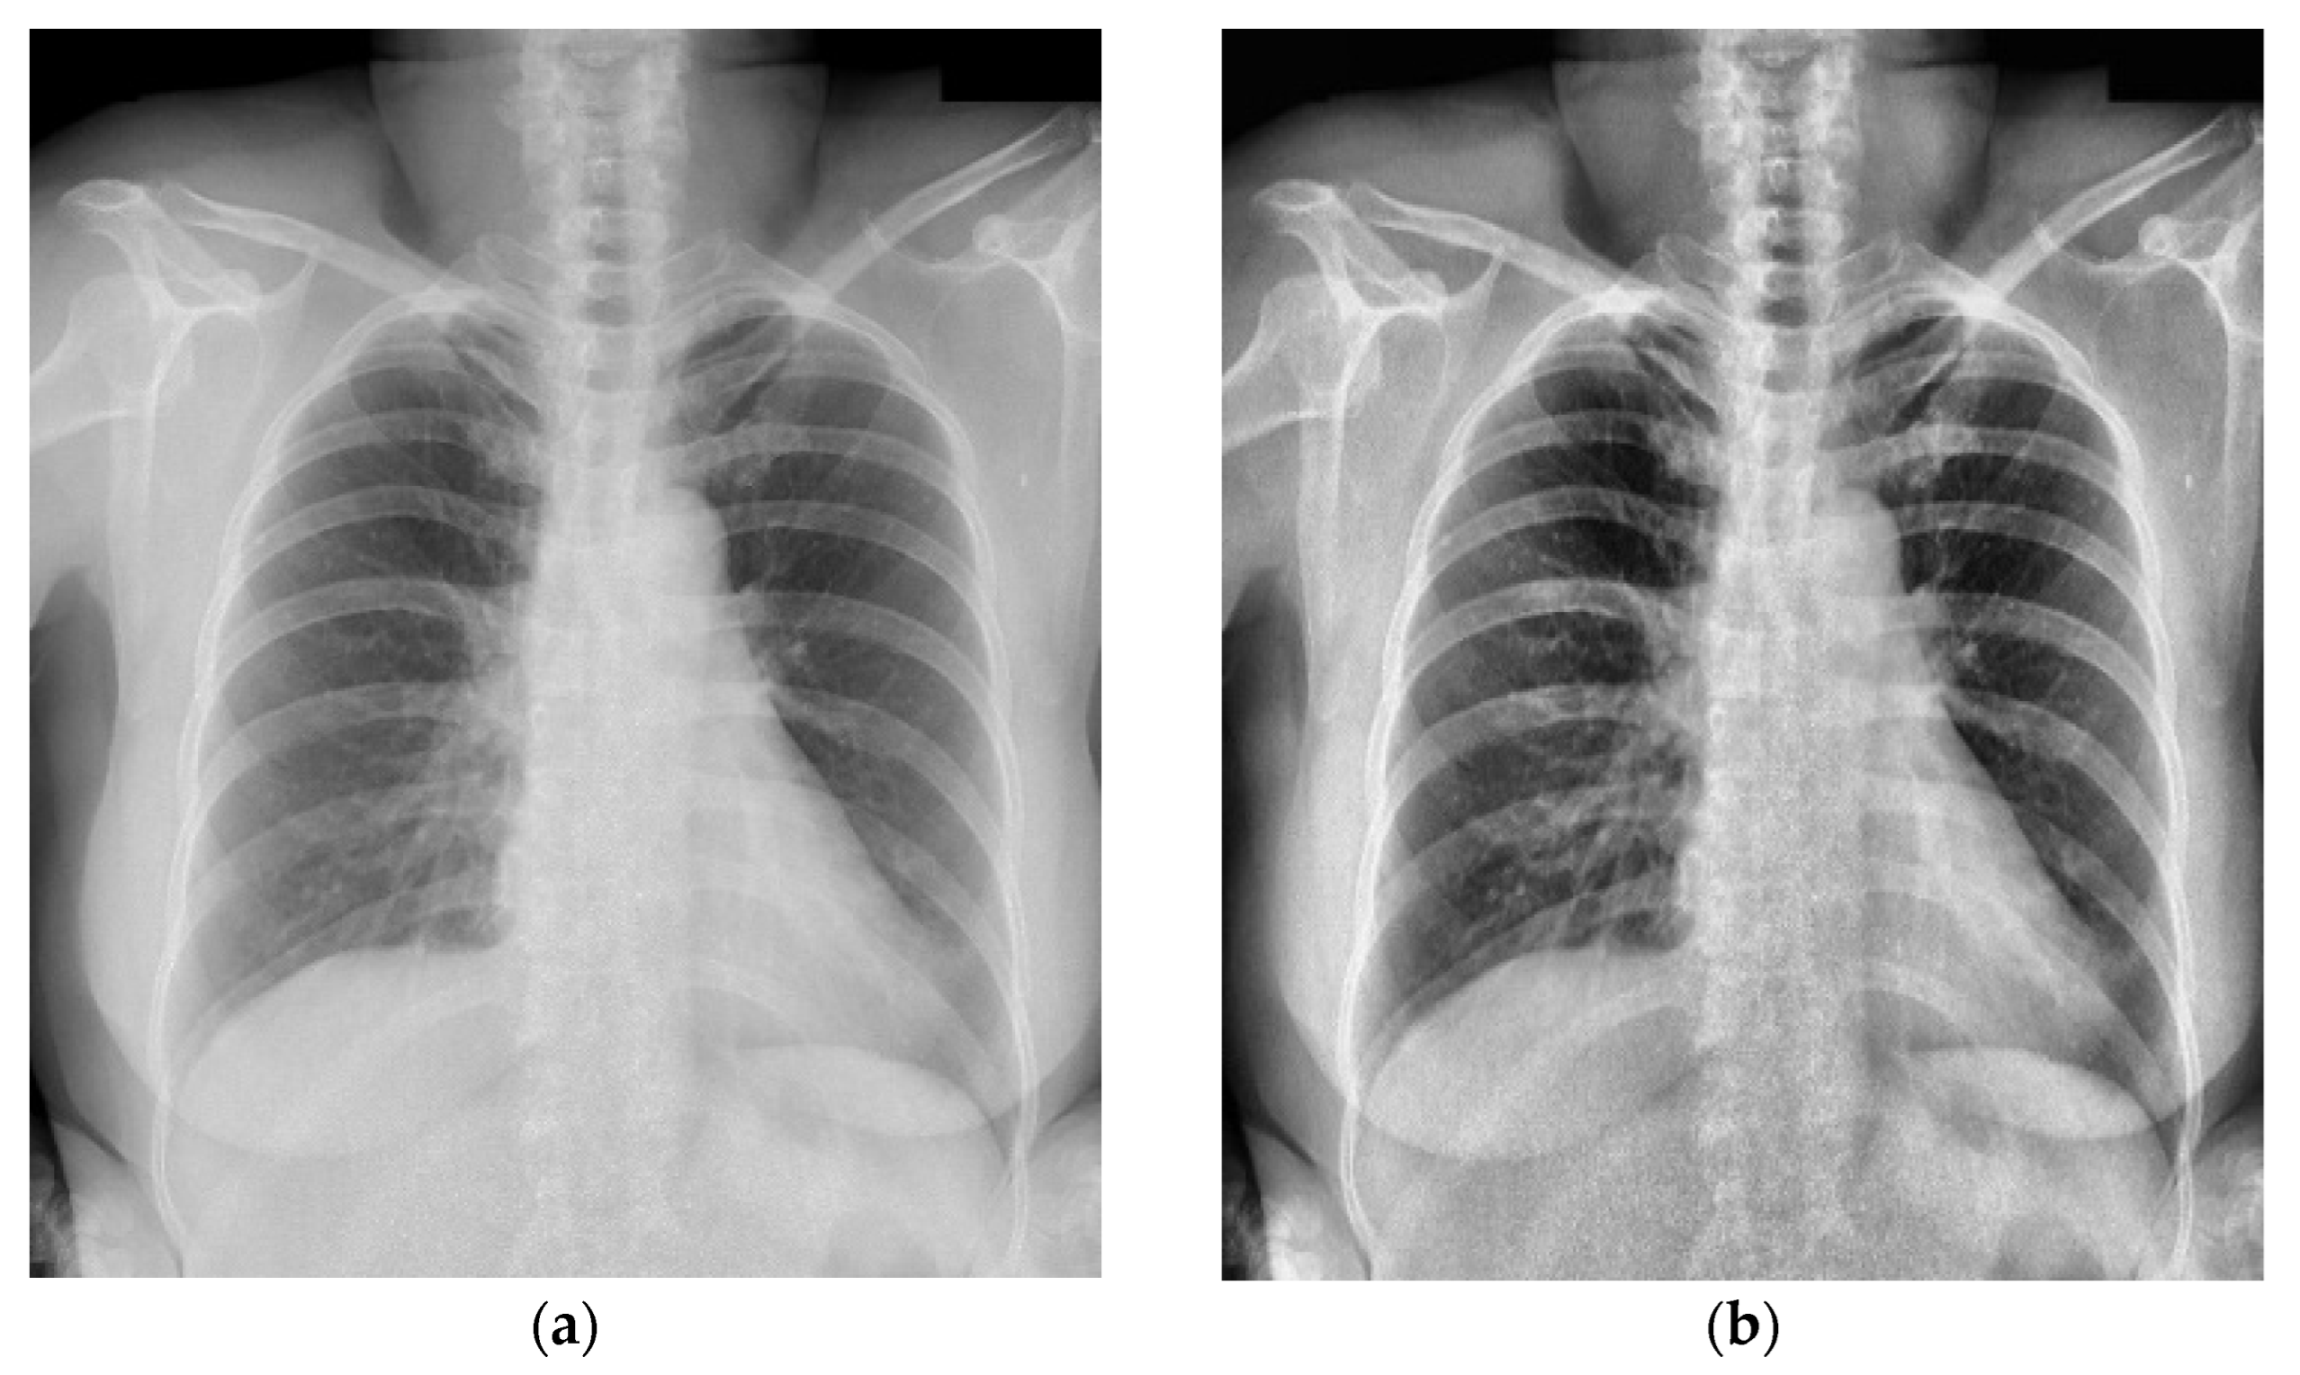

4.1. Experimental Datasets and Pre-Processing